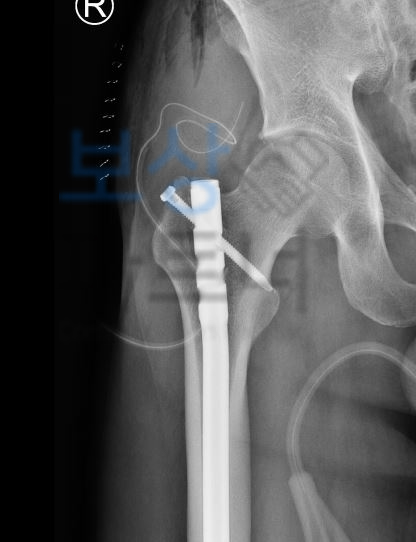

의료용 워커 허리 고관절 골절 인공관절 치환술 장해 사고로 인해 허리 골절, 고관절 골절, **발목 골절, 인공관절 치환술 **등등 위 진단 중 하나라도 해당 된다면 내 보험에서 상해 후유장해 보상 알아보셔야 합니다.

수술한지 얼마 되지 않았어도 골절로 인해 금속고정술을 할 정도면 장해 보상까지 알아보셔야 하고, 의료용 워커 허리 고관절 골절 인공관절 치환술 장해 특히 허리 골절은 비수술 보존적 치료를 시행하셨어도 후유장해 보상 가능성 있습니다.

실제 보상파트너와 함께 진행했던 보상 사례를 보시면 대퇴부 골절 수술하신 황@@님은

후유장해 보험금 2,000만 원